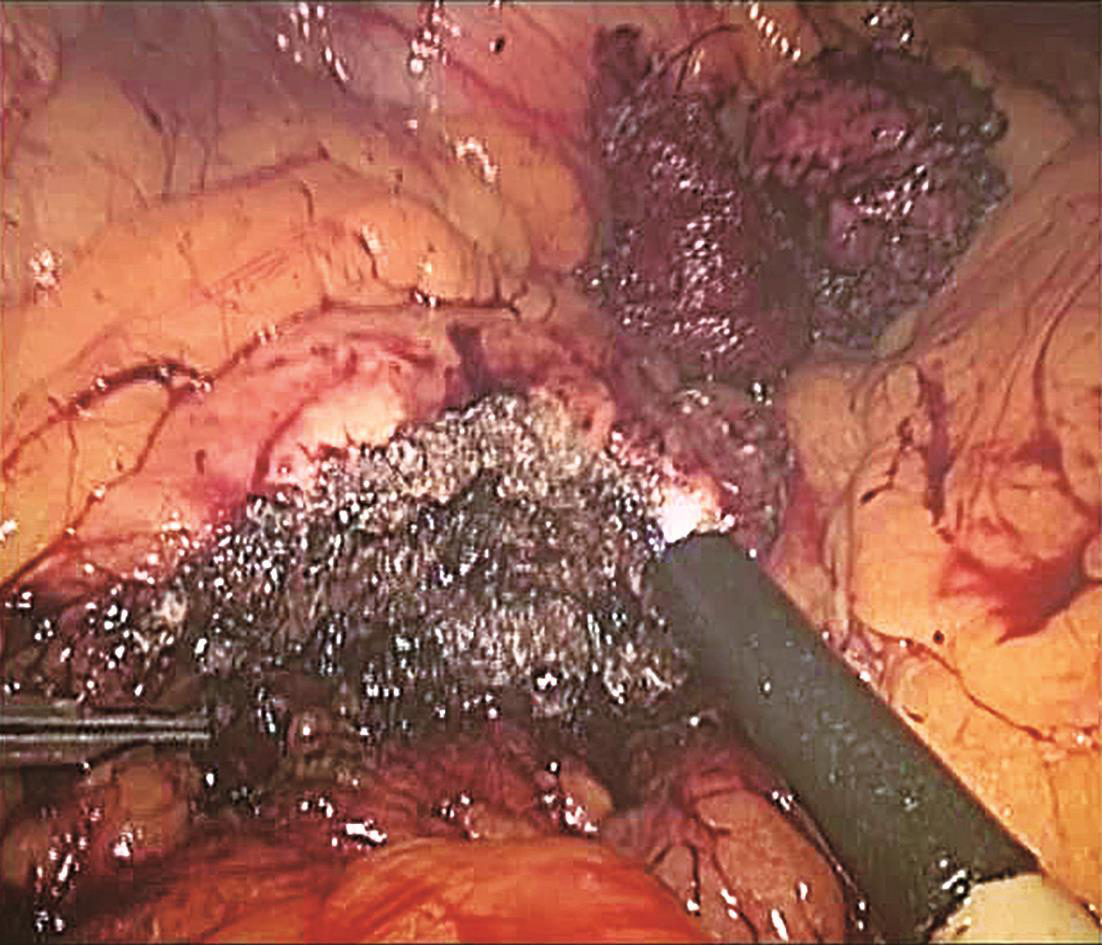

患者取平卧位,头高脚低,四孔或三孔法操作;首先自胃网膜血管弓下方横行打开胃结肠韧带(图6-1),探查胰腺颈、体、尾,必要时可打开胰腺下缘被膜,游离胰腺后方深入探查;清楚定位肿瘤后,镜下缝合肿瘤一针作为牵引用(图6-2),超声刀紧贴肿瘤,完整剜除;检查胰腺创面,选择性缝合创面(图6-3);取出标本,送冰冻,留置引流,关闭腹壁切口,术毕(图6-4)。

图6-3 超声刀完整剜除肿瘤,创面止血